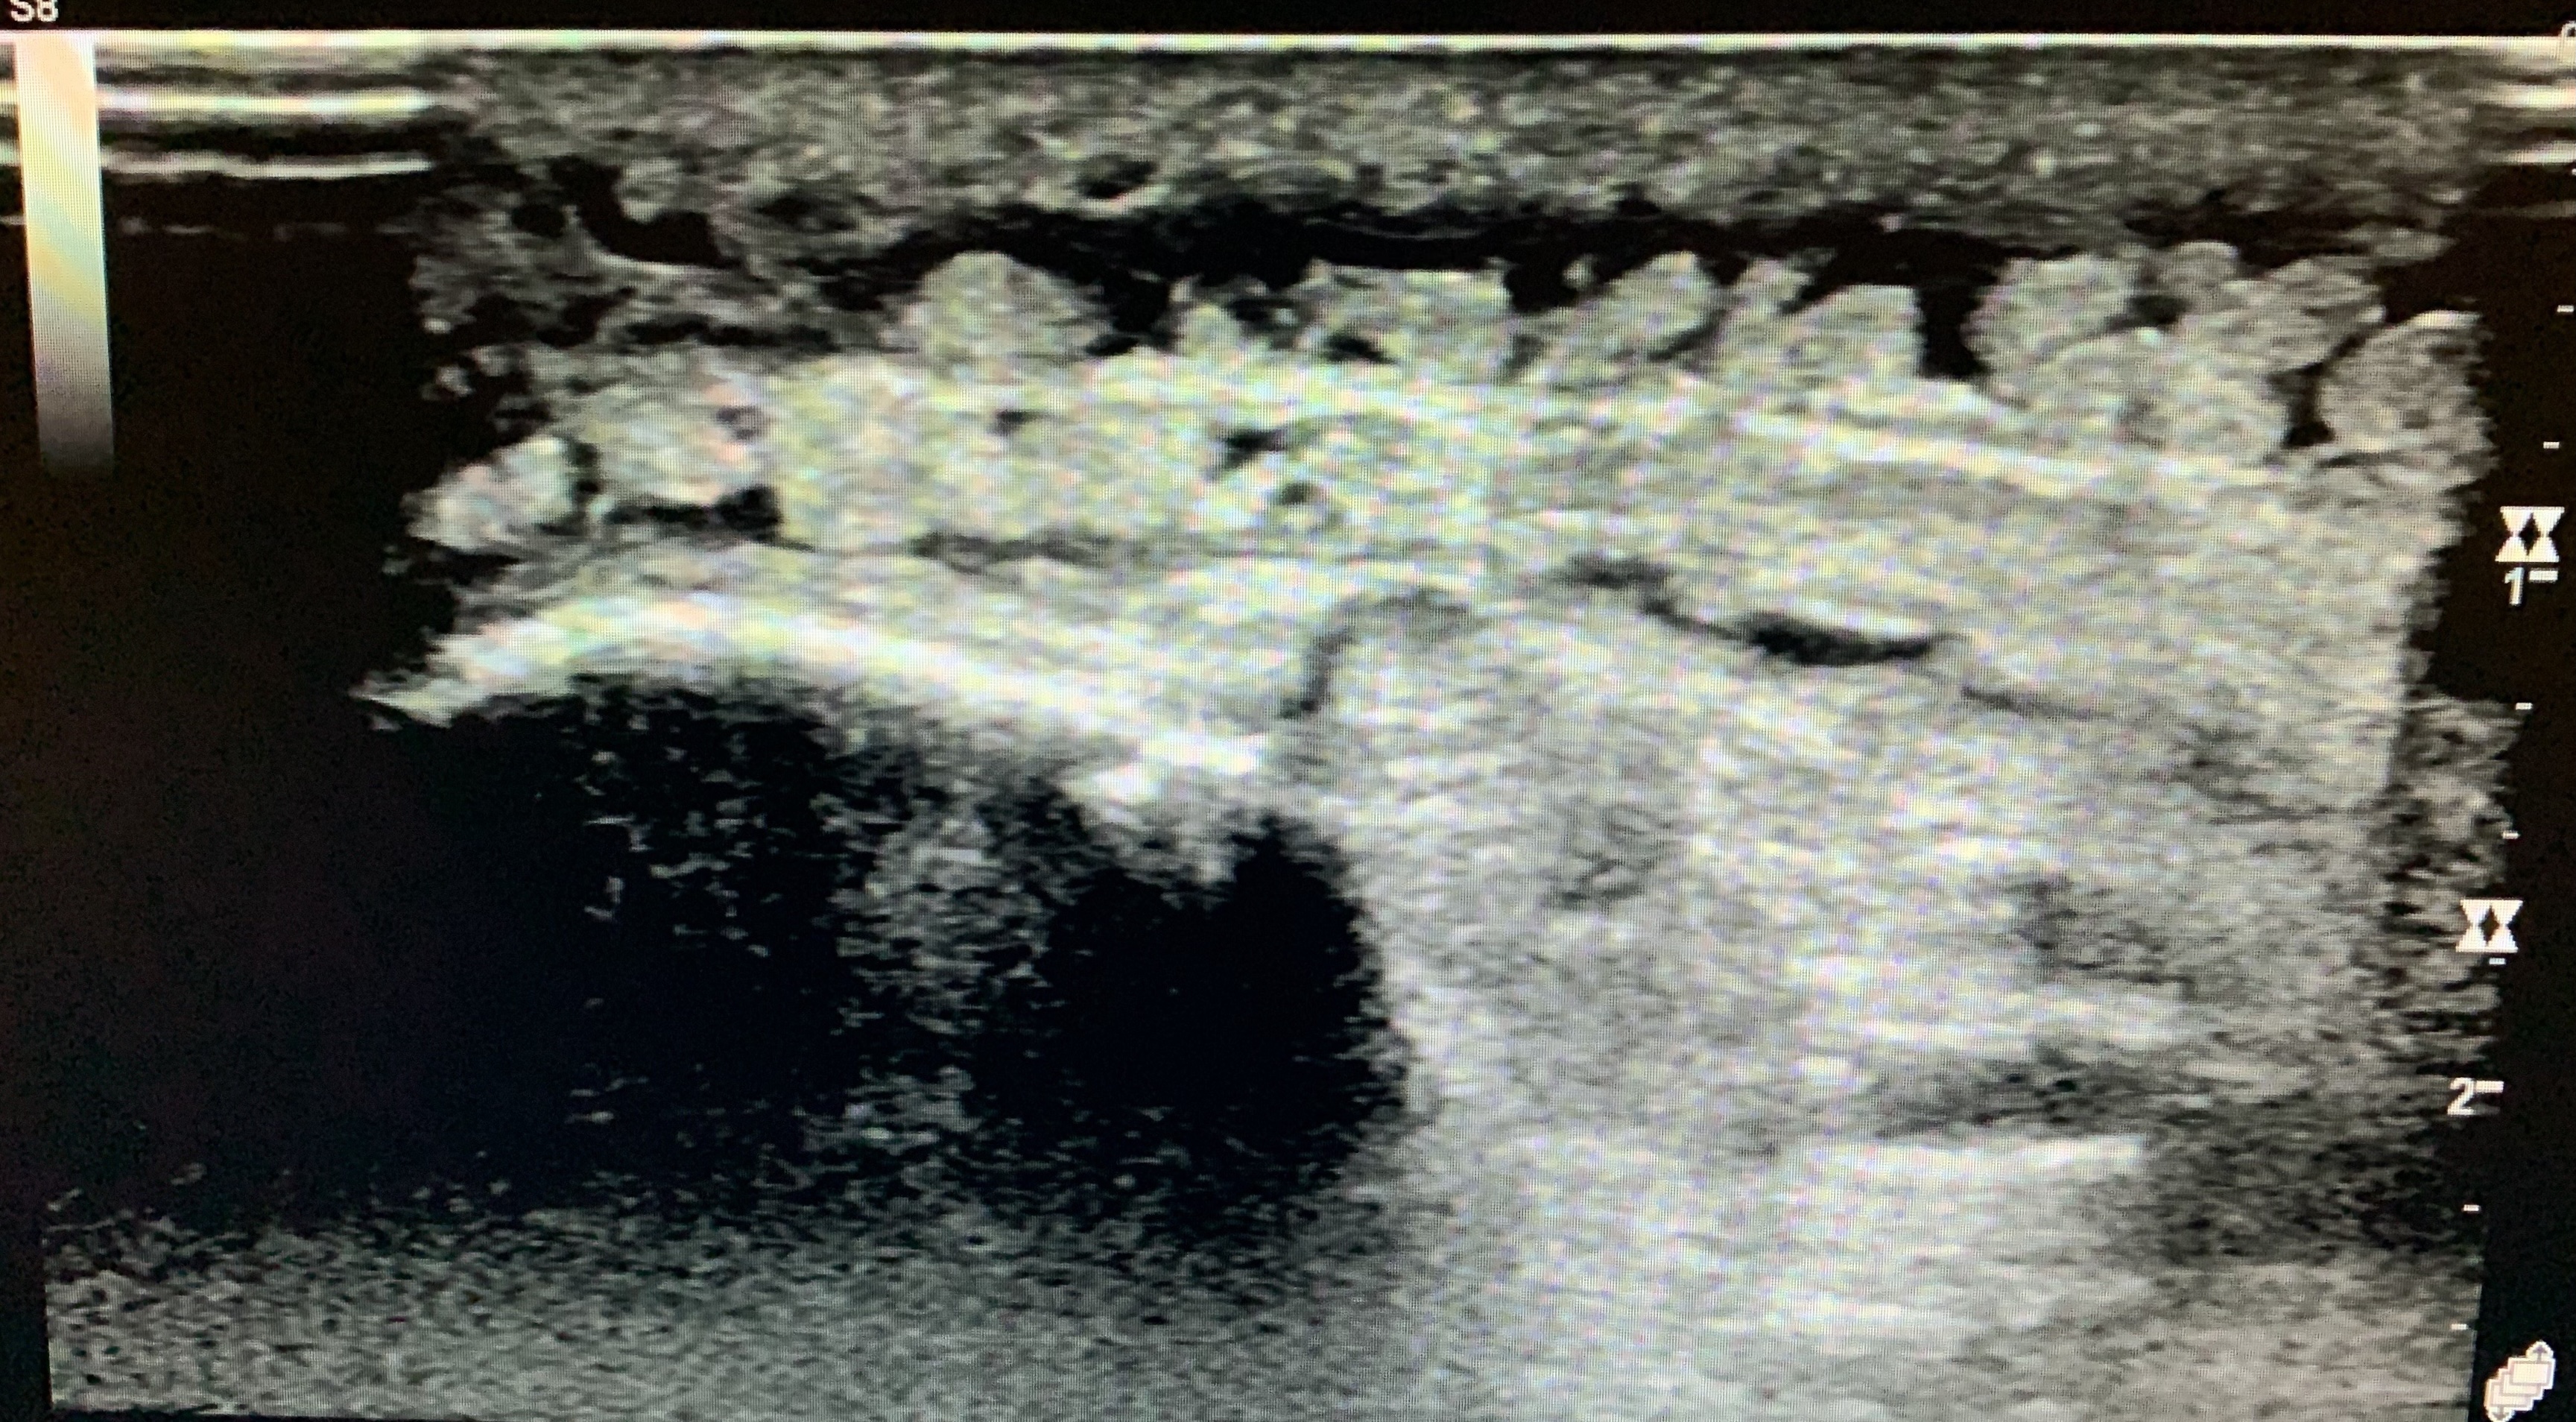

Asses for edema, calcifications, phleoboliths etc.